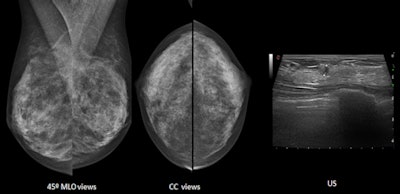

First up, Dr. Fiona Gilbert from the department of radiology at the University of Cambridge in the U.K. will address the "problem child" modality radiologists must deal with on a regular basis: mammography. ECR delegates will learn about the definition of dense breasts and what they look like on mammography. In addition, they will understand the different methods to measure breast density on mammography and analyze details that can be associated with abnormalities in dense tissues.

Breast density can be measured using different techniques such as the Boyd and Cumulus techniques, and there are different scoring systems for assessing the amount of breast density on mammography, particularly the BI-RADS systems, and the Royal College of Radiologists (RCR) breast group system. In addition, quantitative methods are becoming available, such as Volpara and Quantra software.

"The reason these techniques are important is because firstly, and most importantly, an assessment of breast density on mammography gives the reader an indication of sensitivity of the mammogram to detecting breast cancer. BI-RADS 4, BI-RADS D, or 'dense breast' in the U.K., implies that the sensitivity is reduced compared with someone who has fatty breasts or BI-RADS A or I," she said. "There is a masking effect because of dense breast tissue, reducing the likelihood of detecting breast cancer."

Dr. Luis Pina Insausti from the department of radiology at Clinica Universitaria de Navarra in Pamplona, Spain, will discuss ultrasound and dense breasts. Ultrasound can detect additional breast cancers in dense breasts after negative mammography, increasing the detection rate of breast cancer by up to 37%.

The American College of Radiology BI-RADS lexicon describes three patterns for ultrasound breast composition: homogeneous echotexture -- fat, homogeneous echotexture -- fibroglandular, and heterogeneous echotexture. The patterns have similarities with mammographic density patterns (dense mammographic patterns can be seen as homogenous echotexture -- fibroglandular and heterogeneous echotexture patterns).

"Due to the fact that most benign and malignant lesions are usually seen as hypoechoic masses, these lesions are better detected on homogeneous echotexture -- fibroglandular than on the other patterns," he added.